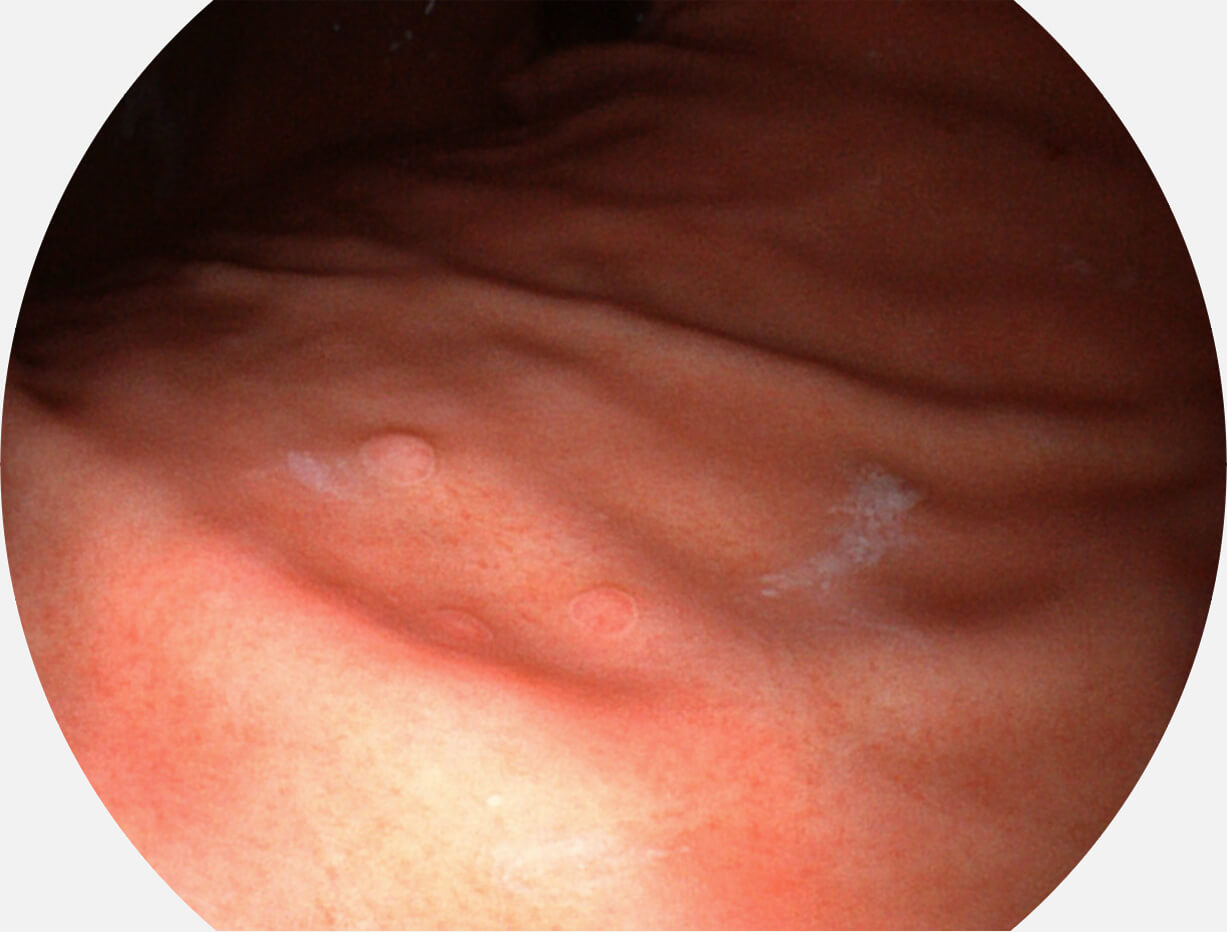

图像具有高亮度、高黏膜血管颜色对比度的特点,且不改变粘液、食物残渣、粪便的基本颜色,可在中远景下进行观察,助力消化道早期疾病的诊断。

白光图像

SFI图像